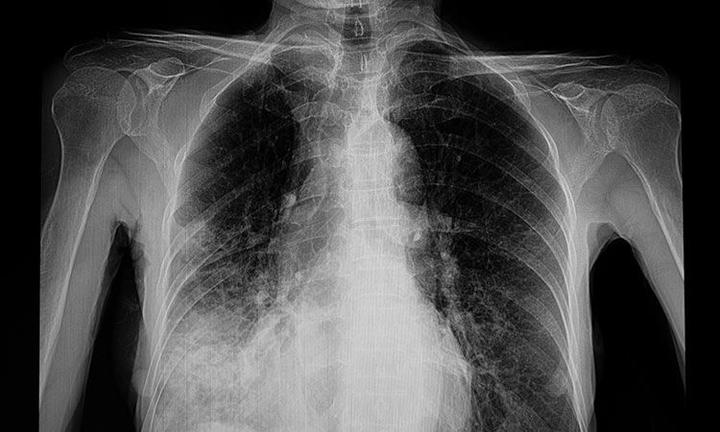

Po dotarciu do pediatry, lekarz zazwyczaj sugeruje kilka badań, aby dokonać trafnej diagnozy. Oczywiście, w grę wchodzi osłuchiwaniu klatki piersiowej, a czasami także RTG, chociaż coraz częściej zastępuje je USG. Warto być przygotowanym na to, że lekarz może zlecić dodatkowe badania laboratoryjne, które pomogą określić, czy w organizmie malucha znajdują się bakterie, wirusy czy inne patogeny. Im szybciej postawimy diagnozę, tym prędzej dzieciak wróci do pełni sił, co stanowi naszą główną misję!

Pediatra to prawdziwy superbohater w białym fartuchu, który potrafi skutecznie zdiagnozować przyczyny problemów zdrowotnych malucha. Dzięki starannemu wywiadowi medycznemu oraz badaniu fizykalnemu, lekarz precyzyjnie oceni sytuację, która zachodzi w płucach. W niektórych przypadkach konieczne będą dodatkowe badania, takie jak RTG – nie martw się, to nie jest czarodziejskie zaklęcie, lecz kluczowy krok w procesie leczenia! Zrozumienie, jaki typ zapalenia występuje – bakteryjny, wirusowy czy może grzybiczy – umożliwi wdrożenie odpowiedniej terapii, co przyspieszy powrót dziecka do zdrowia.